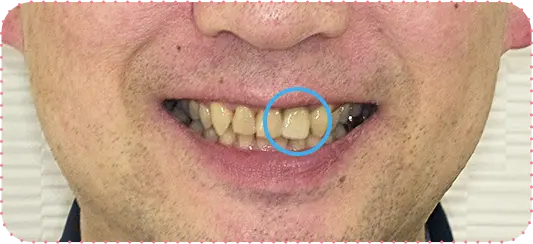

Before

After

主訴

上の前歯が抜けそう

治療期間

6か月

治療費

30万円

治療内容

右上1番を抜歯後に骨と歯茎を増やし、隣の歯の裏側を少量削り、接着性ブリッジにて修復

治療のリスク

咬み合わせによっては、セラミックが欠ける可能性があります。